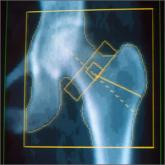

As the population of older adults rises, primary osteoporosis has become a problem of public health significance,...